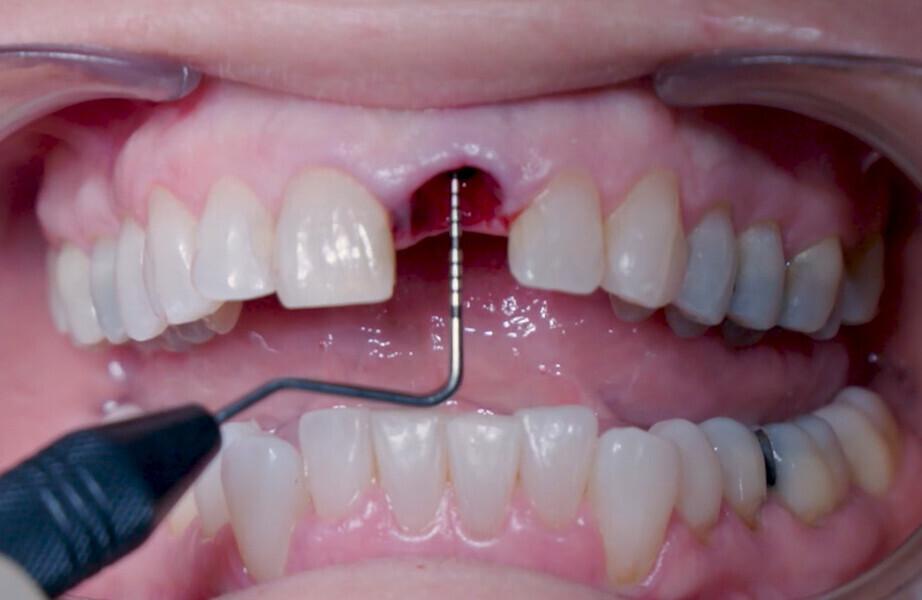

Fig. 12: Final implant position assessment in relation to gingival margins.

Fig. 11: Final implant position assessment.